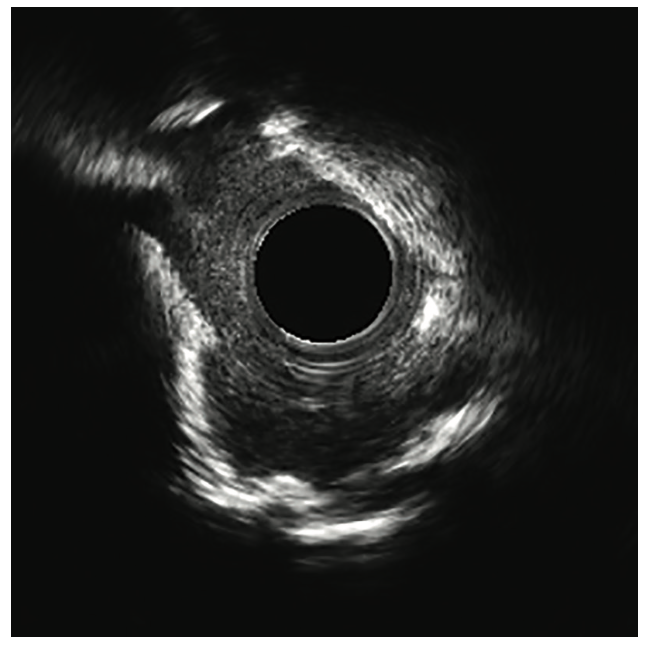

Right radial access was obtained with a radial 7 French (Fr), 10 cm length GLIDESHEATH SLENDER® Introducer Sheath (Terumo Interventional Systems) and the ostium of the LMCA was engaged with a 7 Fr Extra Backup (EBU) 3.5 guide catheter (Medtronic) to facilitate bifurcation stenting. The initial angiogram images revealed a worsening of the distal LMCA stenosis, now at 80% and extending into the ostial LAD (Figure 1). A Runthrough NS Izanai White guidewire was advanced across the lesion into the distal LAD and a Runthrough NS Izanai Blue was advanced across the lesion into the distal LCx with minimal difficulty. To facilitate intravascular ultrasound catheter delivery, the distal LMCA/ostial LCx was predilated with a semicompliant 2.0 mm x 15 mm Takeru PTCA Balloon Dilatation Catheter at nominal pressure (8 atmospheres). IVUS of the LCx was performed first, followed by IVUS of the LAD, and showed severe, concentric calcification of the distal LMCA and ostial LAD/LCx (Figure 2). For plaque modification and lesion optimization prior to stent deployment, a 3.5 mm x 12 mm C2+ intravascular lithotripsy balloon (IVL, Shockwave Medical) was advanced first into the LCx and subsequently into the LAD. The LMCA to proximal LCx and the ostial LAD were treated with 120 pulses with 12 inflations of the IVL balloon. Angiography revealed no evidence of dissection following IVL; however, there was some recoil in the ostial LCx, for which cutting balloon angioplasty was performed with a 3.5 mm x 15 mm Wolverine balloon (Boston Scientific) in the ostial LCx and extending back into the distal left main. Next, the decision was made to proceed with bifurcation stenting using a culotte strategy. A 3.5 mm x 20 mm Synergy Megatron drug-eluting stent (DES, Boston Scientific) was placed from the distal LMCA into the proximal LCx (Figure 3). Following post dilation of the DES with a 3.5 mm x 15 mm noncompliant balloon, a new Runthrough NS Izanai White was used to re-wire the LAD through a side strut of the LMCA-LCx DES. A semicompliant 3.0 mm x 12 mm Takeru PTCA Balloon Dilatation Catheter crossed into the LAD with minimal difficulty and was used to dilate the stent struts to facilitate delivery of the LMCA-LAD DES. A noncompliant 3.0 mm x 15 mm balloon inflation was performed to optimize the LAD lesion further. A 3.5 mm x 16 mm Synergy Megatron DES was then placed in the proximal LAD, overlapping with the prior stent in the LMCA (Figure 4). Following post dilation of the LMCA-LAD DES with a 3.5 mm x 15 mm noncompliant balloon, the proximal portion was optimized (proximal optimization technique [POT]) with a 4.0 mm x 8 mm noncompliant balloon. The LCx was then rewired with the Runthrough NS Izanai White through a side strut of the LMCA-LAD stent and the Runthrough NS Izanai Blue was placed in the LAD. Following serial dilations of the LMCA-LAD stent struts with Takeru PTCA Balloon Dilatation Catheters, kissing balloon inflation of both the LAD and LCx extending back into the LMCA was performed with a 3.5 mm x 15 mm noncompliant balloon in the LCx and a 3.0 mm x 15 mm noncompliant balloon in the LAD (Figure 5). Repeat IVUS of both stents back into the LMCA was performed, demonstrating adequately expanded and apposed stents with no evidence of edge dissection. Final POT was performed in the LMCA with a 4.5 mm x 8 mm noncompliant balloon. Final angiography revealed TIMI-III flow, no evidence of proximal or distal edge dissections, no perforation, and <5% residual stenosis (Figure 6). The total contrast volume was 55 mL with a case length of 1.5 hours. The patient was discharged three days later without complication.